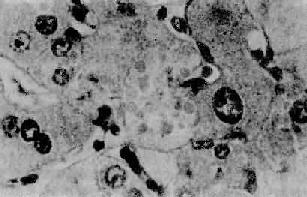

四、酒精性肝病酒精性肝病(alcoholic liver disease)为慢性酒精中毒的主要表现之一。长期大量酗酒者据统计有10%~20%发生此类损伤。严重时出现临床表现,如呕吐、呕血或黑便,其中部分可发生黄疸、肝功能衰竭。 【病变】 慢性酒精中毒主要引起肝的3种损伤,即脂肪肝、酒精性肝炎和酒精性肝硬变。三者可单独出现,也可同时并存或先后移行。一般认为脂肪肝在先,或经过酒精性肝炎再演变为肝硬变,或直接演变为肝硬变。 1.脂肪肝酒精中毒最常见的肝病变是脂肪变性。肝细胞含有相当大的脂滴,可将胞核推挤到细胞一侧,肝细胞肿大变圆。小叶中央区受累明显,有时同时伴有各种程度的肝细胞水样变性。单纯的脂肪肝常无症状。 2.酒精性肝炎(alcoholic hepatitis)在有临床肝症状表现的病例,常出现3种病变:肝细胞脂肪变性,酒精透明小体(alcoholic hyalin,AH 图10-42)形成和灶状肝细胞坏死伴中性粒细胞浸润。

图10-42 酒精性肝炎 图中央区肝细胞浆内见成群的酒精透明小体 3.酒精性肝硬变(alcoholic cirrhosis) 一般认为此种肝硬变是由脂肪肝和酒精性肝炎进展而来。一般的脂肪肝,如继续酗酒则多发展为酒精性炎,再演变为肝硬变。酒精性肝炎时肝细胞发生坏死,最终引起纤维化。相邻肝小叶的纤维化条索相互连接,导致肝小叶的正常结构被分割破坏,发展成假小叶及肝细胞结节状再生,形成酒精性肝硬变。 【发病机制】 肝是酒精代谢、降解的主要场所。酒精对肝有直接损伤作用。其机制如下: 1.NADH对NAD比值增高的效应进入肝内的酒精,在乙醇脱氢酶和微粒体乙醇氧化酶系的作用下转变为乙醛,再转变为乙酸。后一反应使辅酶Ⅰ(NAD)转变为还原型辅酶Ⅰ(NADH),因而NADH/NAD值增高。①NADH增多有抑制线粒体三羧酸循环的作用,从而使肝细胞对脂肪酸的氧化能力降低,可引起脂肪在肝内堆积而发生脂肪肝。②NADH增多可使细胞代谢中的乳酸增多,后者对肝内脂肪变及胶原形成等有促进作用。③NADH增多,使线粒体增加以NADH的再氧化,致耗氧过多。肝细胞因缺氧而易于发生坏死和纤维化。 2.乙醛的毒性作用在酒精代谢过程中产生的乙醛具有强烈的生化反应和毒性,可影响肝细胞膜的性状及抑制肝细胞合成的蛋白的分泌排出。 3.营养缺乏作用嗜酒者常有的营养不足,尤其是蛋白质缺乏,使肝内氨基酸及酶类减少,可以促进酒精的毒性作用。